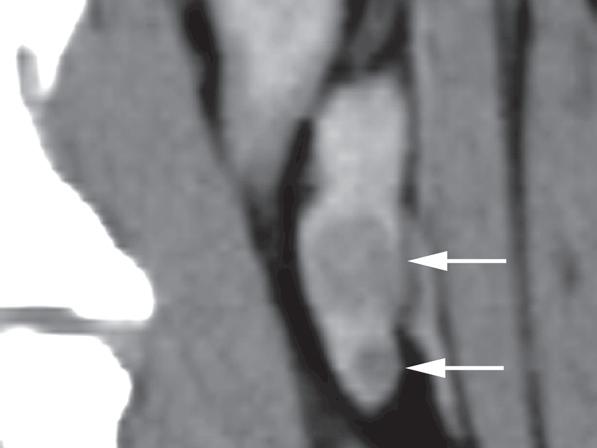

Rycina 1.11.6. Rak tarczycy i gruczolak tarczycy (pies) TK

Badanie wykonano u 12-letniej, kastrowanej samicy owczarka australijskiego z prawostronną masą w dobrzusznej części szyi. Badanie USG wykazało dużą, litą, unaczynioną masę w obrębie prawego płata tarczycy (a) oraz mniejszą, hipoechogeniczną masę w obrębie lewego płata (b). Obrazy TK przed i po podaniu środka kontrastowego (c–f) ułożone od doczaszkowych do doogonowych ukazują dużą, prawostronną, jednorodnie wzmacniającą się masę (c–f – duża strzałka) z niewyraźną granicą dobrzuszną oraz pozatorebkowym szerzeniem się i rozlanym wzmocnieniem pokontrastowym przyległych tkanek (e, f – grot strzałki). W obrazie bardziej doczaszkowym widoczny jest prawidłowy lewy płat (c, e – mała strzałka), natomiast w obrazie bardziej doogonowym jest on powiększony i ma niższą gęstość, niż można by oczekiwać, co sugeruje obecność drugiej, mniejszej masy (d, f – mała strzałka). W obrazach reformowanych wzdłuż osi długiej widać dwa małe guzki w lewym płacie (h – małe strzałki). Wyniki obrazowe potwierdzono podczas zabiegu (i, j – strzałki). Biopsja wycinkowa wykazała prawostronnego raka tarczycy z naciekaniem pozatorebkowym oraz lewostronnego gruczolaka tarczycy